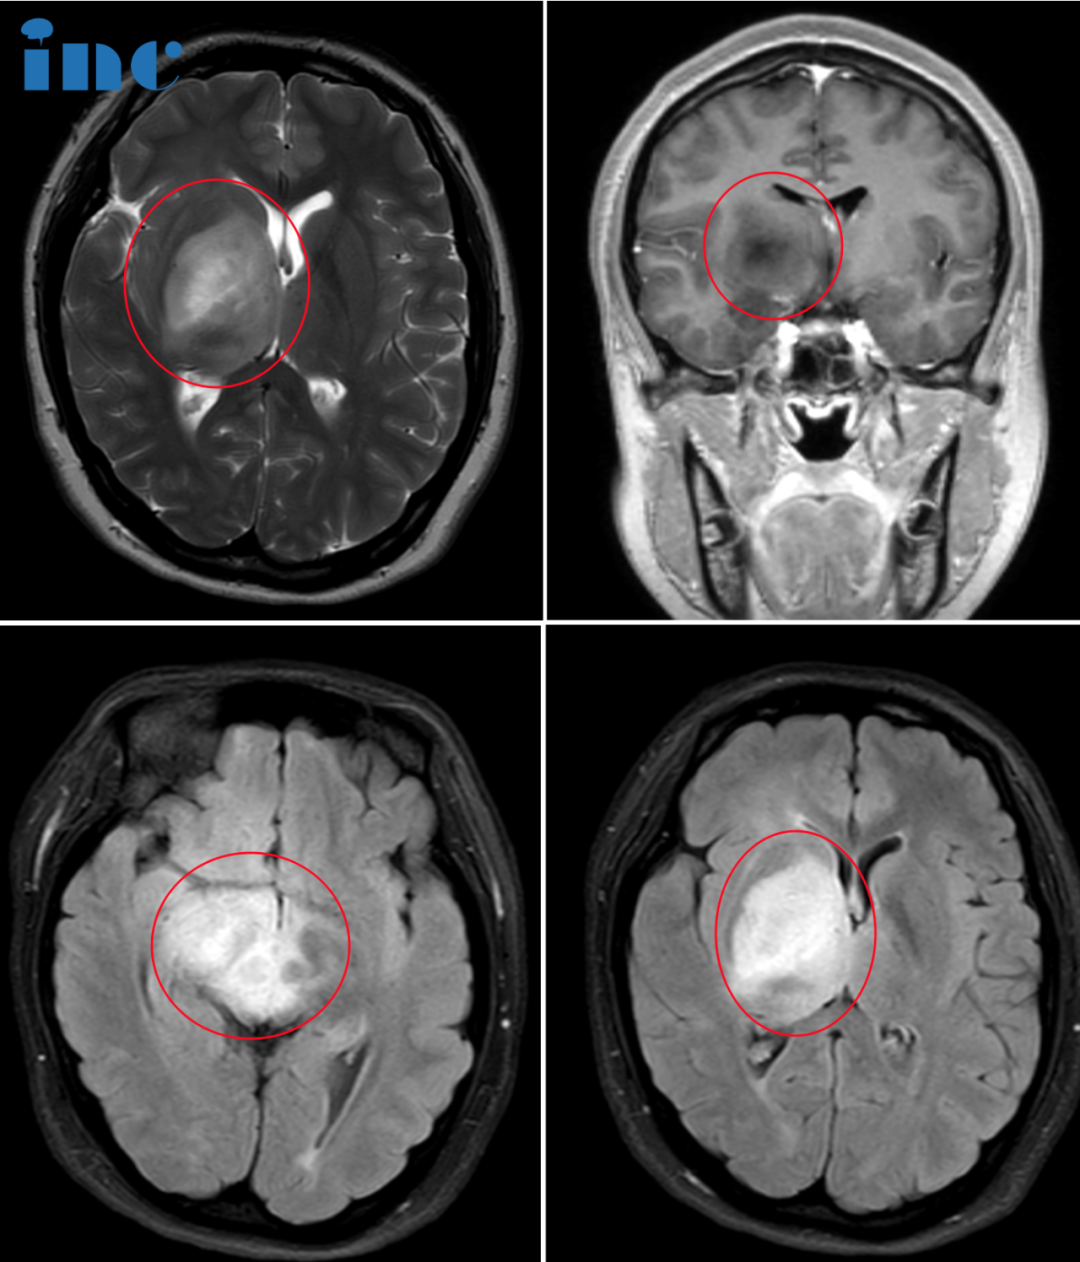

05、17岁女孩,右侧基底节,双侧丘脑及大脑脚,中脑弥漫病变,可以手术吗?

病史摘要:杨先生没想到,17岁的女儿媛媛竟然会得这样的重病。他恨老天的不公,2023年7月底,媛媛出现无明显诱因的头晕呕吐,检查结果正常。到了8月中旬,媛媛母亲观察发现患者左下肢有无力现象,左上肢也有无力现象,此情况至目前已持续时间约15~25天。2023年8月在当地多家医院进行MR脑部检查,均诊断发现脑部右侧基底节区出现占位灶累及中脑,右侧大脑脚。考虑肿瘤性病变,生殖细胞瘤或胶质瘤可能。杨先生起初准备让女儿进行穿刺活检,但听医生说因为肿瘤位置深,穿刺风险也很大。他犹豫了,担心穿刺活检会让女儿情况加重。因为孩子目前除了左上肢无力,左脚走路拖地以及轻微的左侧面瘫症状外,其他都还正常。在得知巴教授9月来华的消息后,他希望能够请他为孩子手术切除肿瘤。

INC巴教授远程评估意见:

这是一个很复杂的病例,因为病灶位于并延伸到基底神经节内。MRI显示病变有占位效应,但没有增强对比,也没有清晰的特征来帮助我们了解这是哪种病变。我不能确定患者是否有肿瘤,因为病变确实也可能对应于局部炎症(不管是什么原因),可能是淋巴瘤或其他。

所以,在这种情况下,我不能提供手术,因为(病灶)位置深,即使活检似乎也很危险,至少对于开颅来说。可能会导致严重的运动障碍,甚至可能导致更多的神经问题。

下一步的治疗可以分两步进行:

1)从短时间(几天)的高剂量类固醇药物开始,然后进行MRI复查(在一些炎症或淋巴瘤中,MRI已经可以看到效果);

2)可能得话进行立体定向活检,这比开放式手术活检在该案例中更有指示性。